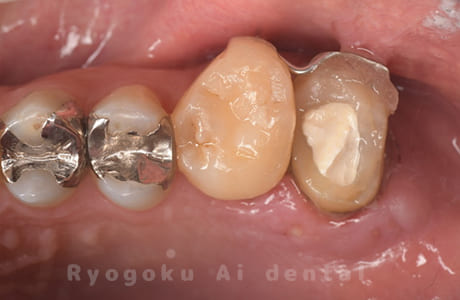

虫歯の治療と銀歯のやり直しを希望され、銀歯を外したところ、虫歯が大きく、神経の処置が必要と判断。患者様と相談し、神経を残す断髄治療となったケース。

<リスク・副作用>

術後は痛み、腫れ、痺れなどの副作用が生じる場合があります。